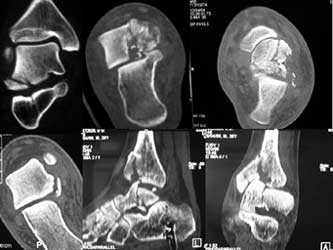

Рис4. а. на КТ перелом таранной и большеберцовой костей, б. на МРТ перелом таранной кости